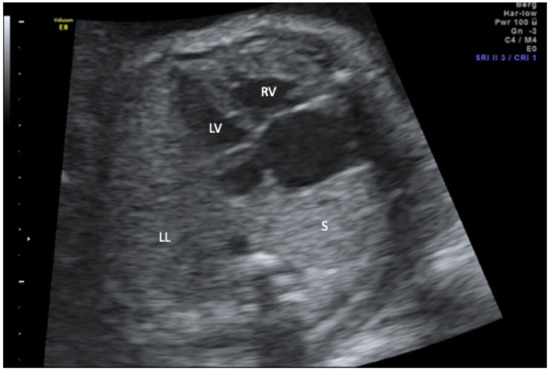

Scimitar syndrome is a rare disease characterized by hypoplasia of the right lung and partial anomalous pulmonary venous drainage to the inferior vena cava. All cases with a prenatal diagnosis of scimitar syndrome with or without associated malformations in an 18-year period (2000–2018) in two large tertiary referral centers (University of Bonn and University of Cologne, Germany) were retrospectively reviewed for the intrauterine course and postnatal outcome. Six cases were diagnosed in the study period. All presented with hypoplasia of the right lung, right-sided mediastinal shift, and abnormal pulmonary venous drainage to the inferior vena cava. Systemic arterial blood supply to the right lung, albeit postnatally present in all cases, could not be detected prenatally. Major associated anomalies were present in all cases and included atrial septal defect (n = 5), coarctation (n = 3), diaphragmatic hernia (n = 2), and VACTERL association (n = 1). Half of the cohort died within 6 months after birth and all three survivors suffer from long-term pulmonary sequelae. The primary hint to the prenatal diagnosis of scimitar syndrome is the abnormal position of the heart in the chest. If searched for, abnormal venous drainage can be identified prenatally and confirms the diagnosis. The prognosis depends on the presence of associated major anomalies and the need for neonatal intervention. Full article

Figure 1